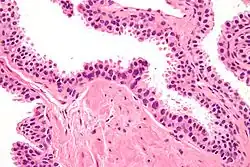

| Micrograph showing high-grade prostatic intraepithelial neoplasia. H&E stain. | |

HGPIN typically has one of four different histologic patterns:[2]

- tufted (fascicular patterning)

- micropapillary,

- cribriform and,

- flat.

Its cytologic features are that of prostatic adenocarcinoma:

- presence of nucleoli,

- increased nuclear-to-cytoplasmic ratio and,

- increased nuclear size.

Microscopically, PIN is a collection of irregular, atypical epithelial cells. The architecture of the glands and ducts remains normal. The epithelial cells proliferate and crowding results in a pseudo-multilayer appearance. They remain fully contained within a prostate acinus (the berry-shaped termination of a gland, where the secretion is produced) or duct. The latter can be demonstrated with special staining techniques (immunohistochemistry for cytokeratins) to identify the basal cells forming the supporting layer of the acinus. In prostate cancer, the abnormal cells spread beyond the boundaries of the acinus and form clusters without basal cells. In HGPIN, the basal cell layer is disrupted but present. PIN is primarily found in the peripheral zone of the prostate (75-80%), rarely in the transition zone (10-15%) and very rarely in the central zone (5%), a distribution that parallels the zonal distribution for prostate carcinoma.[7]